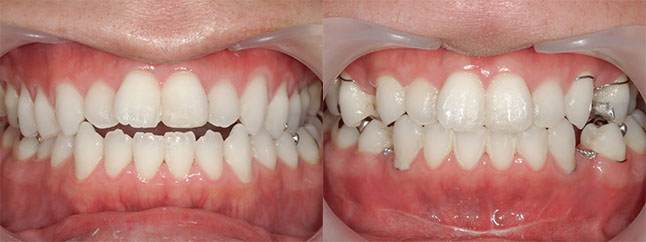

大阪府 22歳 女性

執刀医 辻和志

【治療内容】上のアゴと下のアゴの両方にこんもり感があったため、上下のアゴの骨をきって後ろに下げました。

【費用】上下セットバック 2,307,800円(税込)

【リスク】全身麻酔で行うため全身の健康状態が悪い方は行うことができません。また、手術当日は安静にしていただく必要があります。